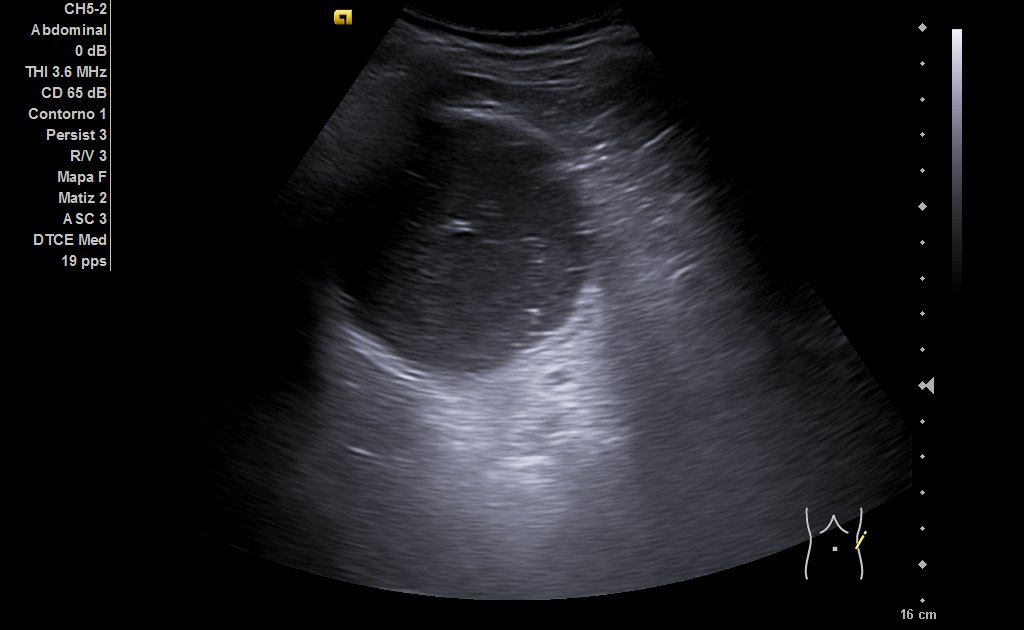

Riñones de tamaño y ecoestructura normales, con buena diferenciación parénquima-seno en polo inferior de riñón derecho, quiste simple de aproximadamente 6 centímetros de eje mayor (ya conocido) y en riñón izquierdo, quiste cortico-sinusal de menos de 2 cm (también conocido). Próstata de 44 gramos. En hipocondrio izquierdo observamos imagen redondeada con contenido ecogénico, con tractos hiperecogénicos en su interior que podría corresponderse a dilatación ángulo esplénico de colon.